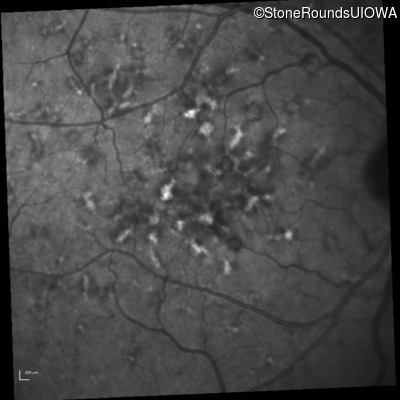

Blue Autofluorescence - Right - 20/20 -1 sc

Exemplar